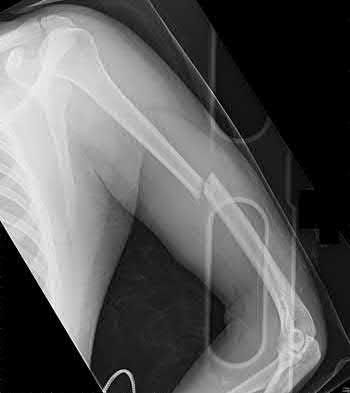

1036) A 68-year-old woman sustains the injury seen in Figure 189 following a fall. Careful neurologic and vascular examinations reveal no associated injury. What is the most common complication of surgical fixation with a locked plate and screw construct through a deltopectoral approach?

5. Screw penetration of the articular surface Corrent answer: 5

Several studies have documented screw penetration through the articular surface as the leading complication with locked plate and screw fixation for displaced proximal humerus fractures. Axillary nerve palsy is rare but can be seen with a deltoid split approach. Whereas some loss of range of shoulder motion is expected following this injury, infection rates about the shoulder are in the 1% to 5% range. While a portion of the deltoid insertion is commonly taken down, complete deltoid insertion detachment has not been described.